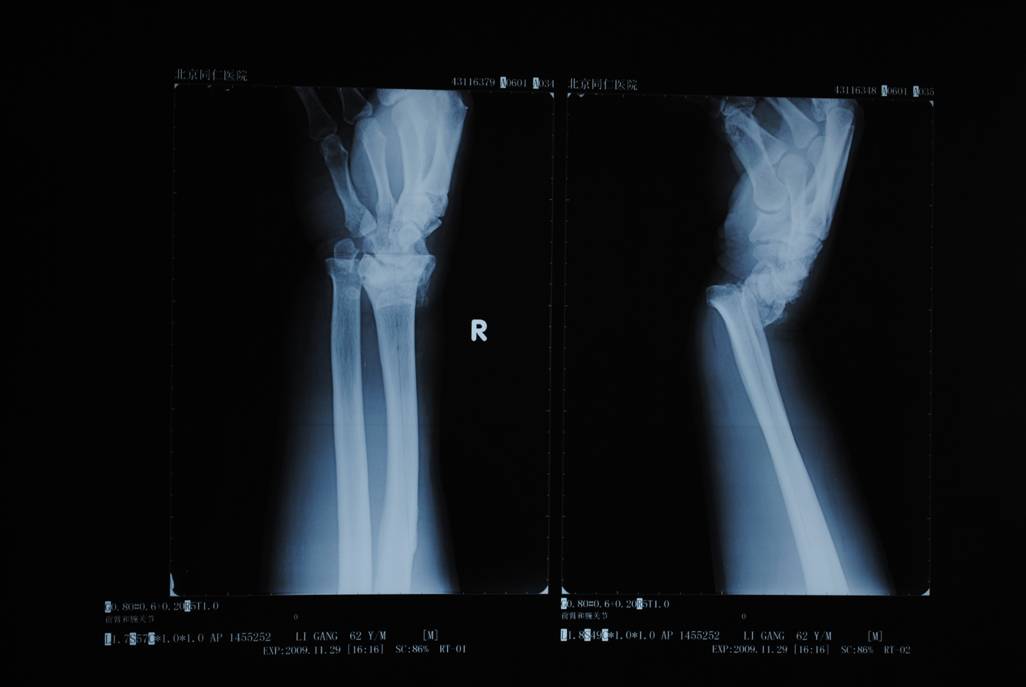

橈骨遠(yuǎn)端骨折術(shù)前

橈骨遠(yuǎn)端骨折術(shù)后

橈骨遠(yuǎn)端骨折術(shù)前 橈骨遠(yuǎn)端骨折術(shù)后